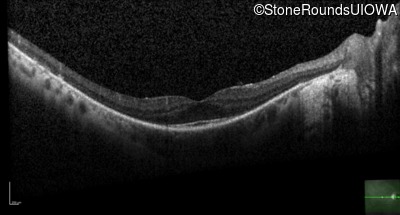

Optical Coherence Tomography - Left - 20/20 -2

Exemplar / OCT Stack

OCT Stack